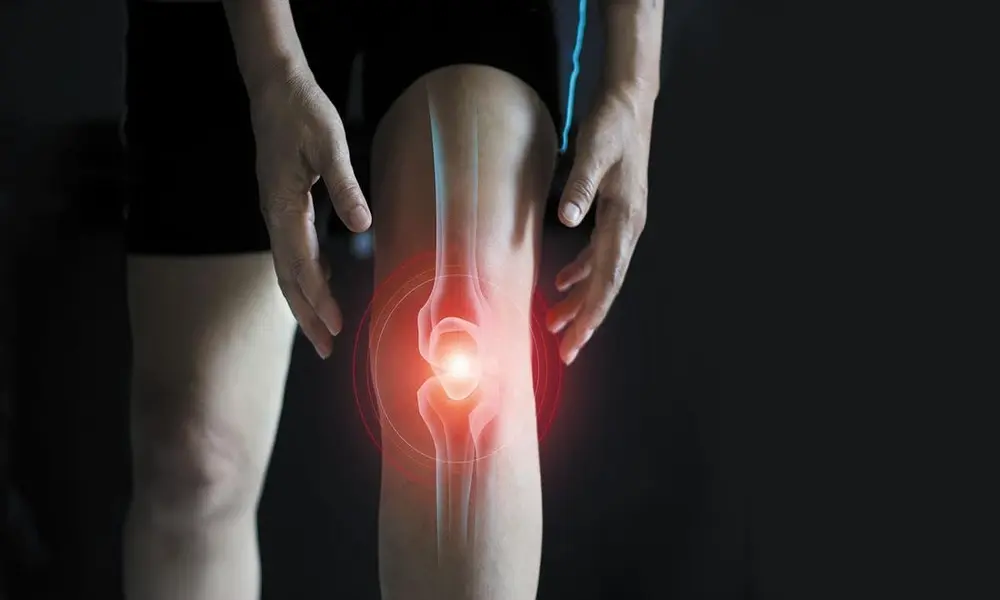

التهاب مفصل زانو 25 آبان 1402

• بیماری ها

التهاب مفصل زانو: علائم، عوامل + راه‌های پیشگیری و درمان